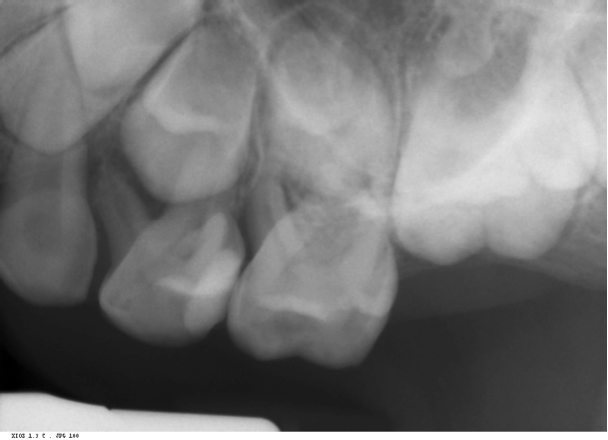

Pre-op image of a primary molar in a 5-year-old patient of Dr. Damas'. Extraction would have resulted in early tooth loss requiring a permanent space maintainer.